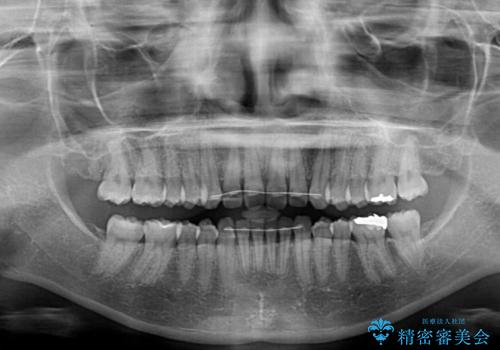

インビザラインによるディープバイトの改善

- 口元の前突感と深い咬み合わせ(ディープバイト)を気にして来院された患者様です。

インビザラインによる上下歯列の遠心移動(後方移動)と、それに伴う近心傾斜(前方傾斜)の改善により、口元の突出感とディープバイトを改善することとしました。

咬合状態が大きく変化したため、治療後半では咬み合わせの位置が定まらなくなりました。上下の前歯に後戻り防止用のワイヤーを装着し、奥歯の咬合をフリーにしたことで1ヶ月ほどで咬み合わせが定まりました。